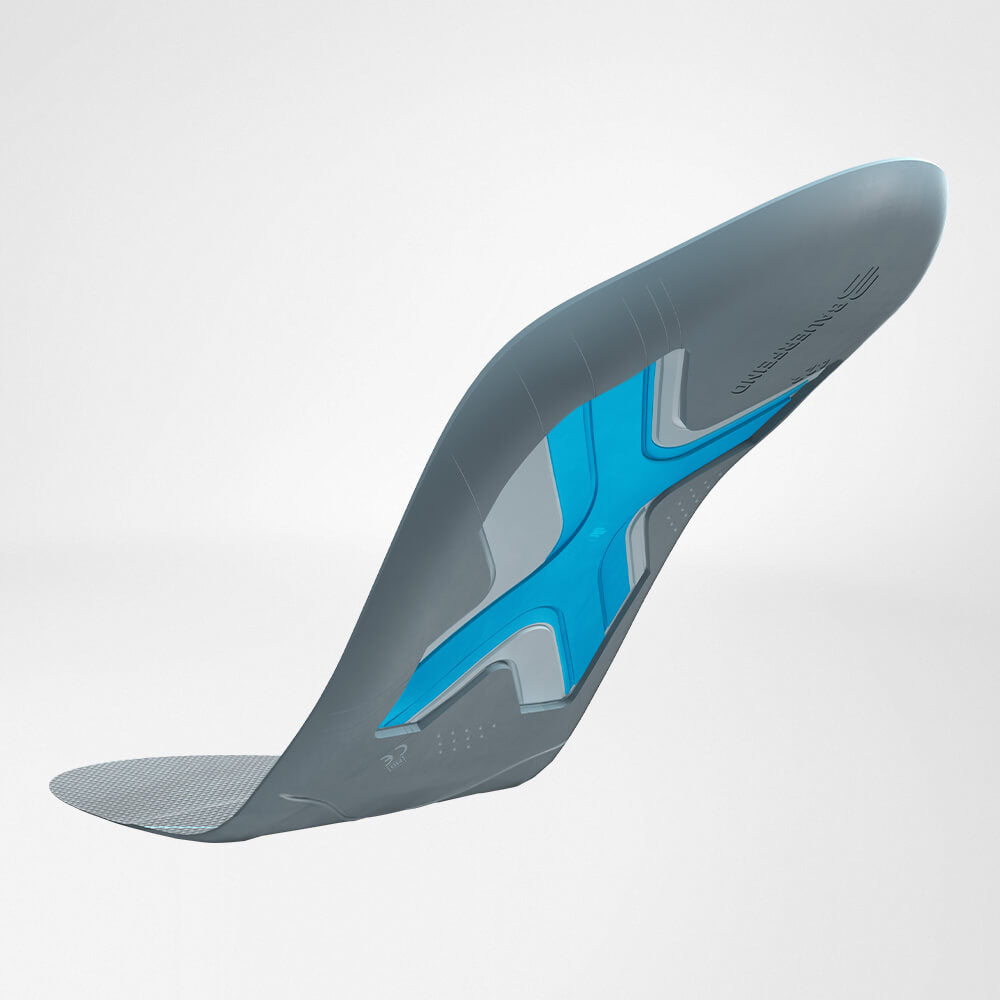

Medical Shoe Inserts

Optimally shaped medical shoe insoles are very effective as both a preventative measure and to slow the degeneration of the Calcaneus (heel bone).

The insoles help protect the foot from excess stress as well as any unnatural movements beyond the natural range of motion, i.e. against overloading and overstretching.

The insoles can also serve as a comfortable cushion for patients with inherent malformations in the structure of the foot.

Best Insoles For Heel Pain

Medical grade shoe inserts like Bauerfeind’s ViscoSpot heel cushion and the ErgoPad Redux Heel 2 insole are designed to alleviate the symptoms of pain in the heel and have been shown to be incredibly effective in this capacity. The insert is designed specifically to adapt to a patient’s foot shape and provide a custom fit.